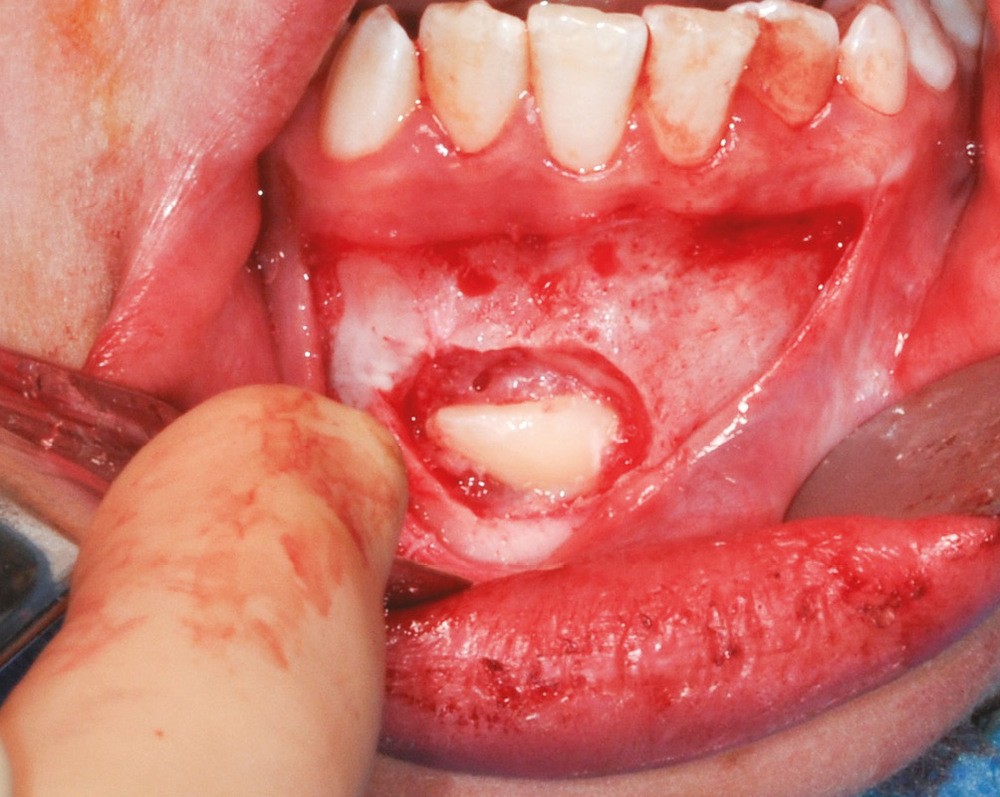

Une avulsion dentaire est un acte chirurgical routinier faisant partie intégrante de l’arsenal thérapeutique de l’omnipraticien. Cet acte peut et doit être décomposé en une succession de plusieurs étapes distinctes. Le succès de la thérapeutique dépend d’une règle simple : ne passer à l’étape suivante qu’une fois la précédente accomplie.

Cet article a pour objectif de reprendre les diverses étapes clés des avulsions dentaires. La connaissance anatomique de la dent et une analyse pré-opératoire de son environnement sont primordiales.

Une notion clé va guider l’ensemble de la séquence chirurgicale : chercher à être le moins traumatique possible. Cela permet à court terme des suites postopératoires sans complications et à moyen terme une cicatrisation optimale.

L’indication de toute avulsion dentaire doit découler d’un plan de traitement global visant un assainissement de la cavité bucco-dentaire, dont le but sera souvent de restaurer ad integrum la fonction de ces dents perdues. Ces extractions doivent donc être les plus atraumatiques possible afin de préserver au mieux les structures environnantes.

Cette cicatrisation se fait de manière centripète depuis les murs apicaux et latéraux de l’alvéole [3]. Le nombre de parois osseuses résiduelles joue donc un rôle important. Dans une optique de préservation tissulaire et de chirurgie a minima, la conservation de l’ensemble des murs osseux entourant la dent à extraire devient alors essentielle.